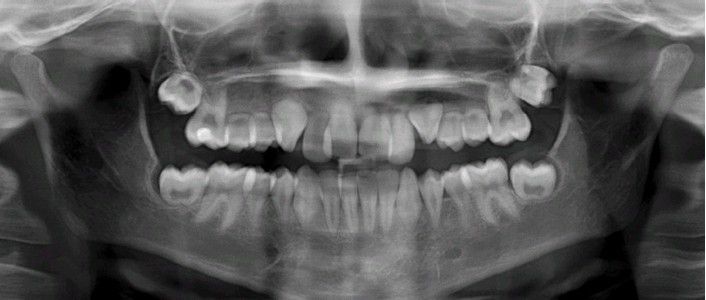

Hypoplasia caused by Antineoplastic therapy

Multiple teeth demonstrating radicular hypoplasia secondary to radiation and chemotherapy for cancer.